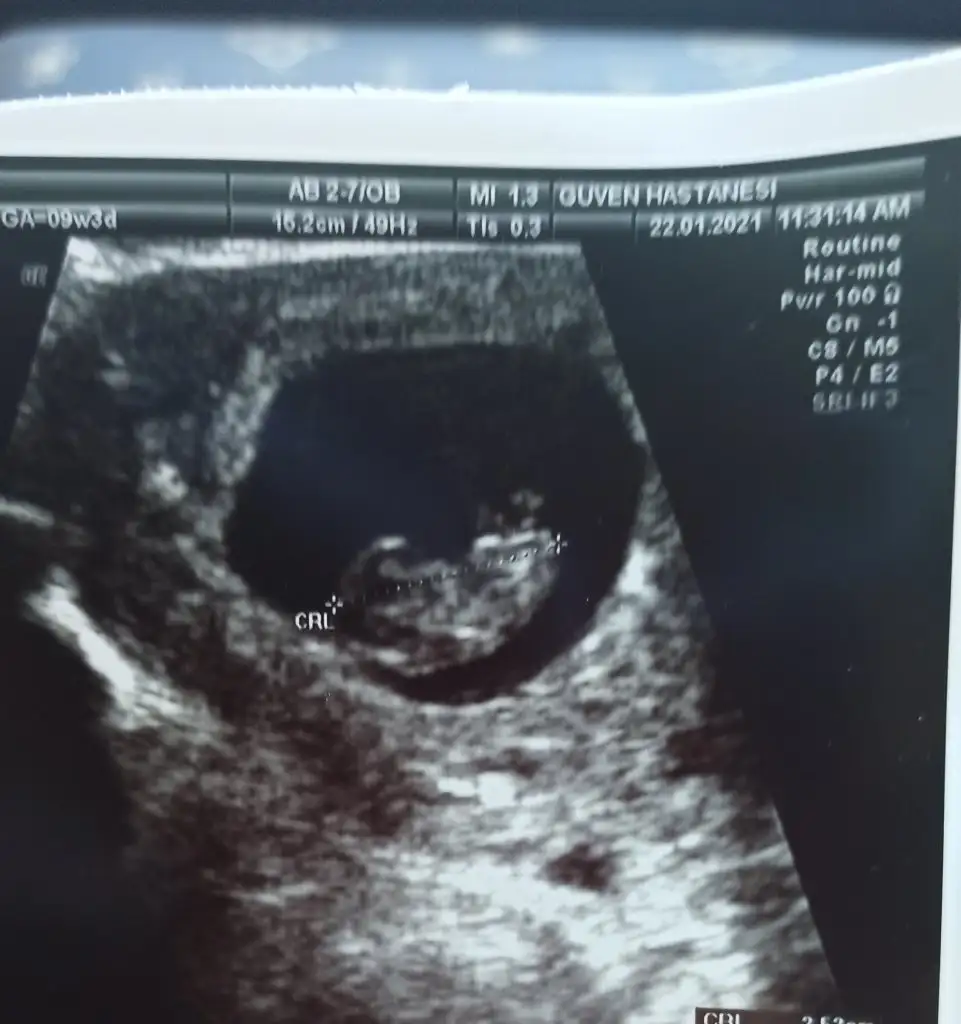

bence kız sağ tarfta plasentaEki Görüntüle 2780164 Eki Görüntüle 2780165 merhabalar bir tahmin de ben isteyeyim 9+3 ve 7+² ye ait fotoğraflar her ikisi de karından usg

Erkek sankiEki Görüntüle 2780164 Eki Görüntüle 2780165 merhabalar bir tahmin de ben isteyeyim 9+3 ve 7+² ye ait fotoğraflar her ikisi de karından usg